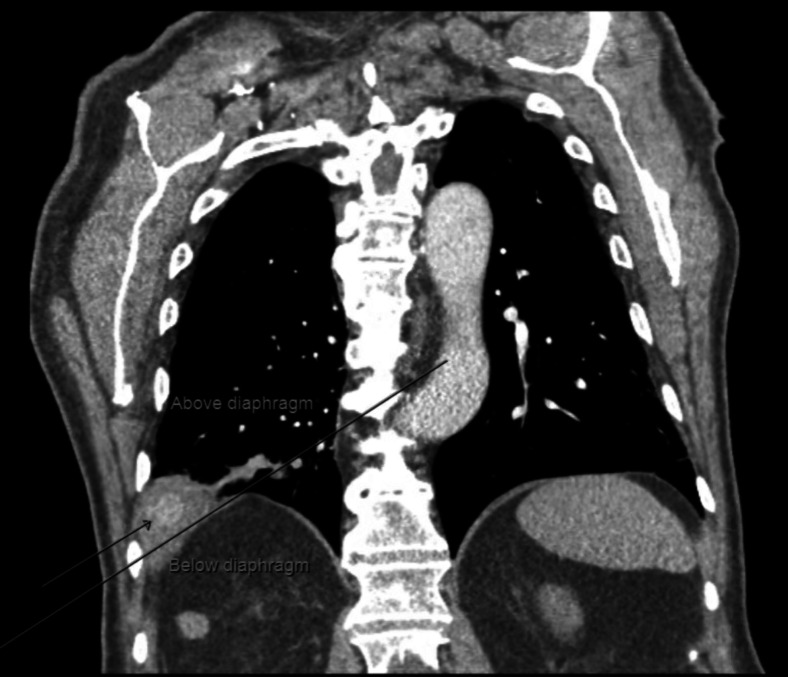

Cholecystectomy, the surgical removal of the gallbladder, is a common abdominal operation often performed laparoscopically due to its minimally invasive nature. Despite its safety and efficacy, rare complications such as gallstone retention outside the biliary system can occur. One unusual complication is the migration of gallstones into the thoracic cavity, potentially causing severe outcomes like pleural effusion, empyema, or bronchopleural fistula, which present diagnostic challenges due to their rarity and varied symptoms. Advanced imaging techniques are essential for diagnosis, while treatment ranges from conservative management for asymptomatic cases to surgical intervention for significant complications. This report details the case of an 80-year-old male who presented with epistaxis and hemoptysis, later found to have a retained thoracic gallstone postcholecystectomy. Despite initial normal imaging and clinical improvement, further investigation revealed a gallstone eroding through the diaphragm into the thoracic cavity. The patient underwent successful thoracoscopic removal of the stone but experienced a prolonged hospital stay due to complications, including atrial fibrillation exacerbation, hemothorax, and lower extremity ischemia. The report underscores the diagnostic complexities of intrathoracic gallstone migration and the severe complications that can arise. A high index of suspicion is necessary for patients with persistent respiratory symptoms following cholecystectomy, and timely imaging and surgical intervention are crucial to minimize morbidity.